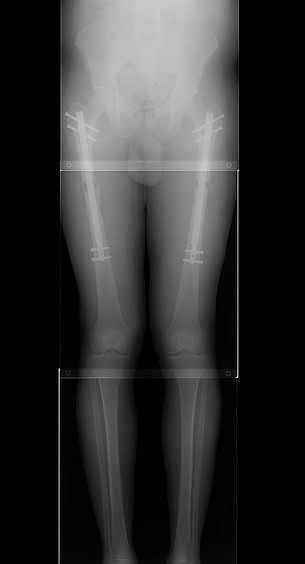

According to Dr. Kevin Debiparshad of The LimbplastX Institute in Las Vegas, the femur-lengthening procedure is only minimally invasive.

Surgeons make four to six incisions in the patient’s thigh before separating the femur with a few incisions. Then, an implant was placed into the hollow of the bone.

The implant can be controlled by the patient with a remote, extending it by a small amount every day until the target length is achieved.